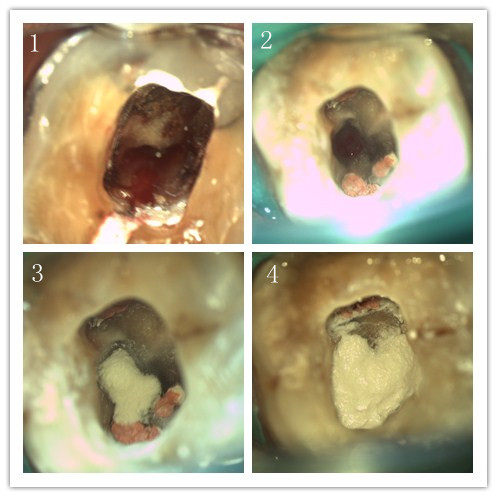

牙体一科开展显微镜下髓腔底穿修补术

患者刘女士因牙疼在外院治疗后效果不佳,仍感反复疼痛,被建议拔除患牙,她抱着试试看的态度来我院就诊。牙体牙髓一科张明副主任医师接诊后,通过详细的牙体检查并拍摄根尖片,确诊其患牙根充不完善且髓室底穿。张明副主任医师为患者重新完善根管治疗后,在显微镜下使用特殊器械清洁髓腔,之后用MTA成功修补了穿孔区,为患者彻底解除了疼痛。治疗结束后刘女士对张明副主任表示了衷心的感谢!

目前,显微镜在口腔临床上已被广泛使用,牙科医生可以在显微镜下确定和评估牙体穿孔的部位和大小,避免操作的盲目性,为患者争取了更多的牙齿保存的机会。(牙体一科 林芸 谢畅畅 供稿图)